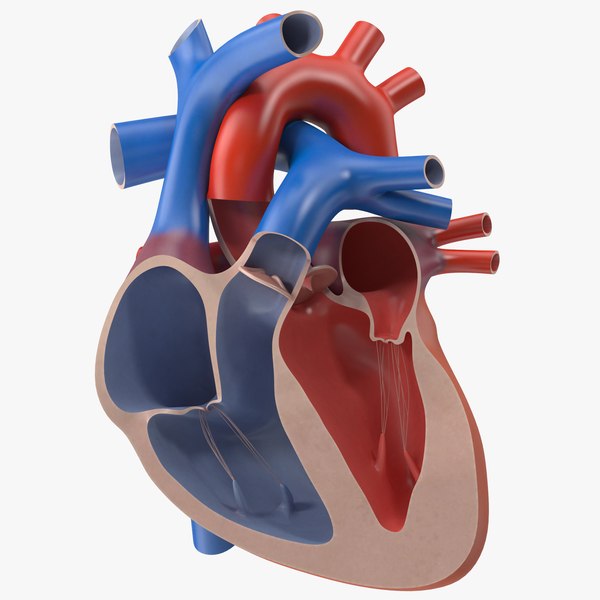

Фотографии и 3D-модели анатомии сердца человека